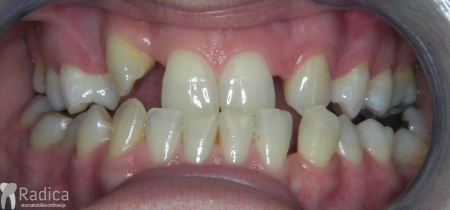

U ovom primjeru pacijent je započeo terapiju nezadovoljan izgledom zuba sa razmacima.